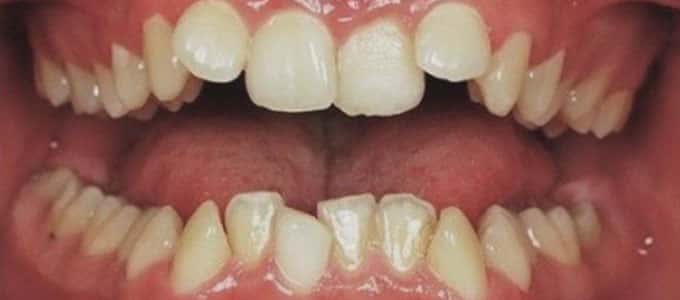

Tratamentul ortodontic este un proces biologic complex care include modificări ale oaselor maxilare, faciale și ale țesuturilor moi pe măsură ce dinții sunt mișcați în noile poziții.

Tratamentul ortodontic nu este o soluție rapidă. Acesta începe întotdeauna cu o examinare minuțioasă a dinților, a buzelor și a întregului aspect facial, sunt necesare radiografii si fotografii de diagnostic. Din aceste informații detaliate medicul ortodont dezvoltă un plan de tratament personalizat.